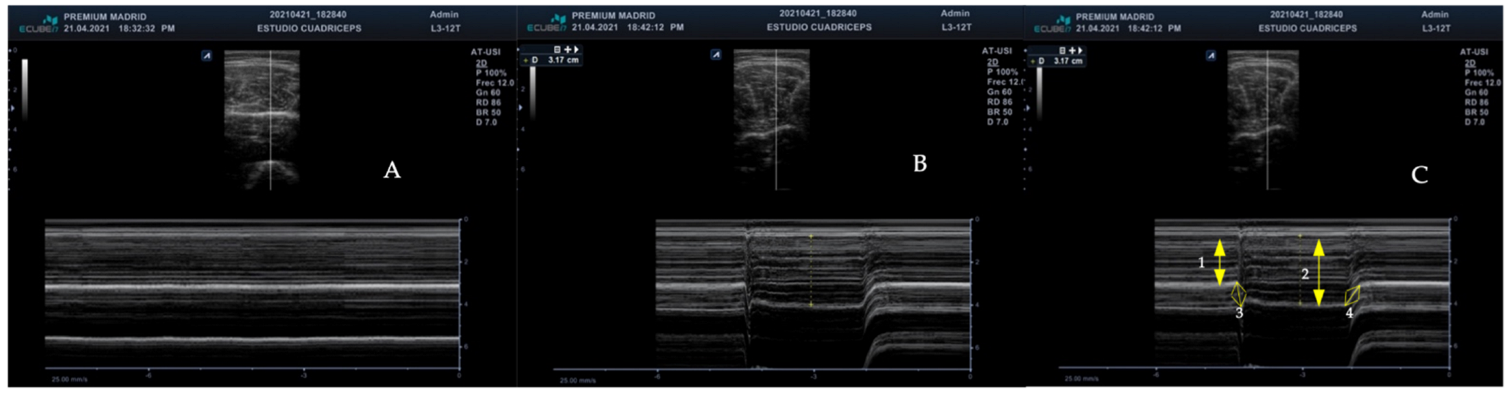

2.3.1. Measurements